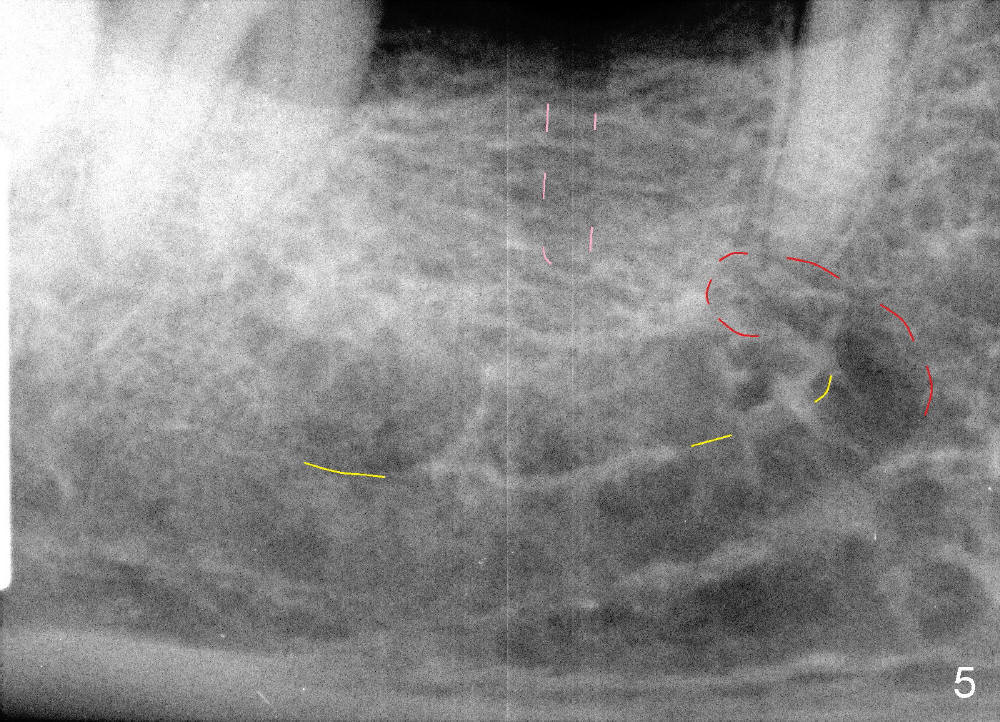

When a positioning pin is placed in the osteotomy with 10 mm deep, the sensor cannot be placed deep enough because of pin interference so no IAC is visible (Fig.4). When the pin is removed and the sensor is placed low enough, IAC is clearly shown, but the osteotomy is barely visible (Fig.5 pink dashed line). With information obtained from pre- (Fig.2,3) and intra- (Fig.4,5) op PA, twelve mm of osteotomy appears to be appropriate. A final implant (5.3x12 mm) is placed with separation from IAC (Fig.6, insertion torque 50 Ncm). A healing abutment is placed (Fig.7,8), which helps retain perio dressing (Fig.9). Two weeks later, the gingiva heals around the abutment (Fig.10). Four months postop, the implant appears to osteointegrate (Fig.11). A cemented abutment is placed (Fig.12). With supragingival margin, oral hygiene is easily maintained (Fig.13). Due to delayed placement, the gingival embrasure is extremely large (*). The issue is much less with immediate implant.